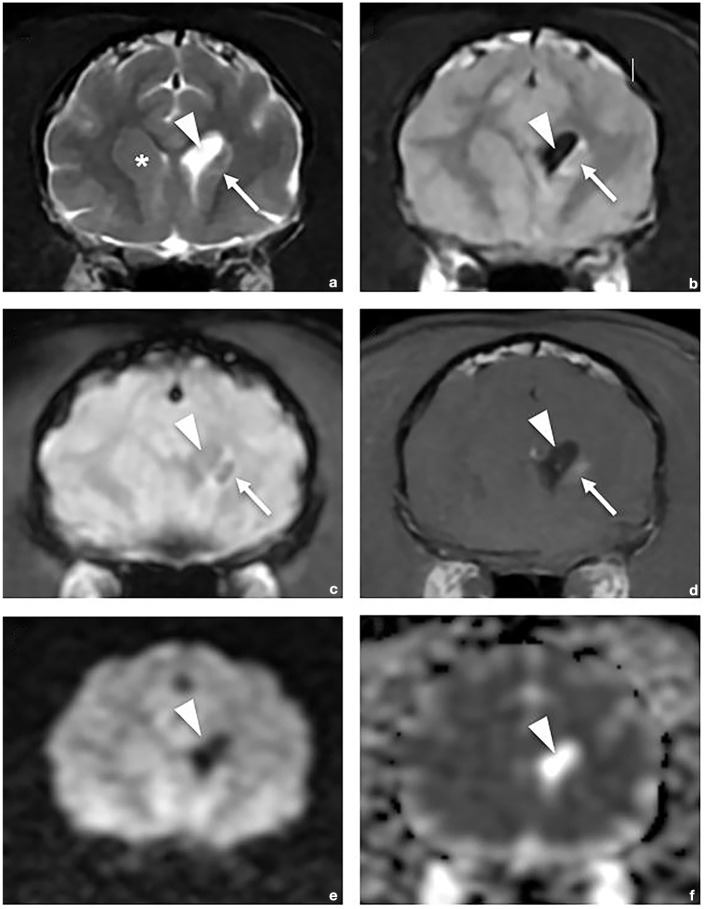

Clinical and MRI findings of hemorrhagic infarcts in two cats with positive outcomes.

Case series summary: A 1.5-year-old male neutered domestic shorthair cat presented with an acute onset of lethargy and difficulty jumping. Prior medical history included a restrictive perimembranous ventricular septal defect and mild mitral regurgitation. Neurologic examination showed left hemiparesis and absent menace in the left eye. MRI revealed a lesion in the right frontal lobe and caudate nucleus with intralesional hemorrhage and restricted diffusion consistent with hemorrhagic infarct. A 6-year-old male neutered domestic shorthair cat presented with three neurologic episodes over 3 months, one consisting of circling to the right, absent menace in the right eye and right-sided postural reaction deficits, and the other two consisting of vestibular signs. MRI revealed a chronic hemorrhagic infarct of the left caudate nucleus. Both cats demonstrated favorable recovery, with cat 2 experiencing a fourth event 9 months after MRI.

Relevance and novel information: This case series details the first two cases of feline hemorrhagic infarct with ante-mortem diagnosis, MRI findings and recovery with a good long-term outcome. Hemorrhagic infarcts, uncommonly reported in companion animals, are a subtype of stroke involving hemorrhage resulting from reperfusion or collateral circulation into an ischemic area of brain tissue. This report discusses typical MRI findings in humans, including differentiation from intracerebral hemorrhage, and the potential role of comorbidities on the development and outcome of hemorrhagic infarcts in cats.